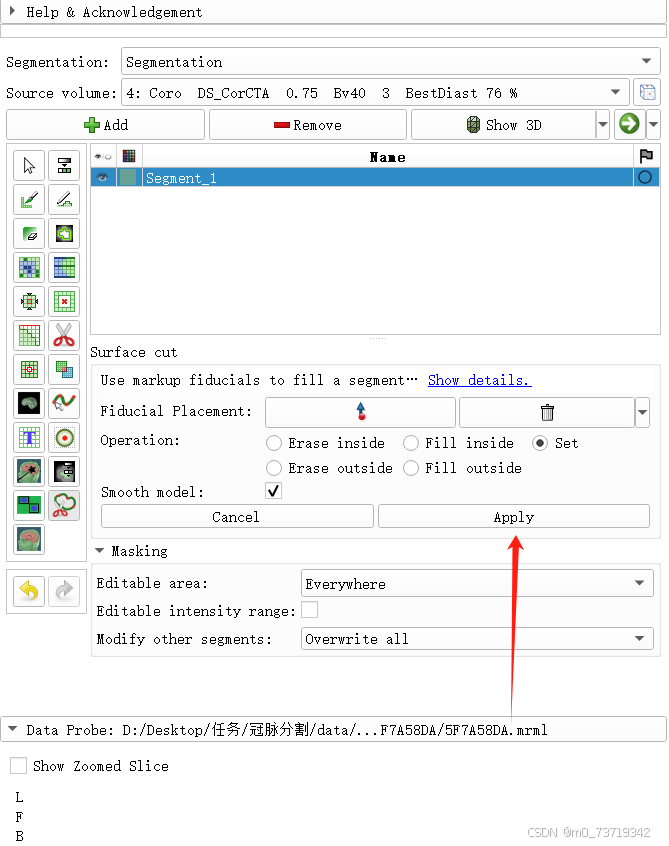

圈完后点击apply完成三维心包分割

然后依次点击下图所示按钮

可见三维图像中分割完毕